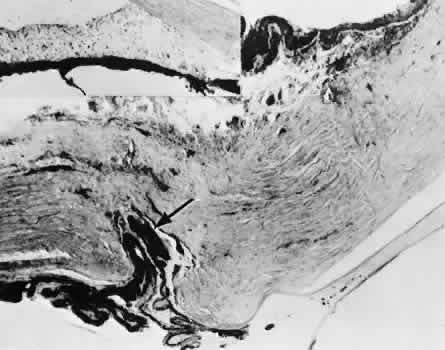

Cyclodialysis (Fig. 21) creates a cleft between the sclera and the longitudinal muscle of the ciliary body. Aqueous passes directly from the anterior chamber into the suprachoroidal space. Histologically, the longitudinal muscle of the ciliary body is disinserted from the scleral spur. Diaphanous tissue often is present in the suprachoroidal space along the route of filtration. The presence of this tissue differentiates the surgical site from artifactual disinsertion of the ciliary body, which is a common artifact of ocular tissue preparation.

Fig. 21. Light micrograph of cyclodialysis. The region of the surgical cleft between the longitudinal muscle of the ciliary body and the sclera (arrow) is filled with delicate fibrous tissue. Note the posterior location of the anterior face of the ciliary body and the angle recesses in relationship to the scleral spur (S).